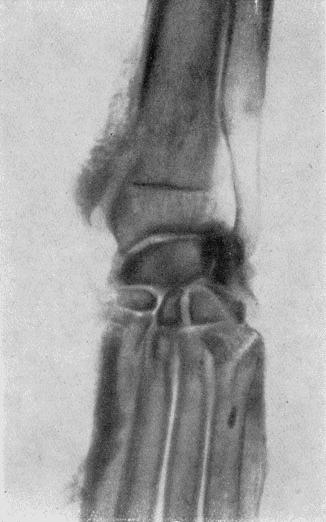

Диагноз острого перикардита в начале заболевания поставить бывает трудно, так как основное заболевание выступает на первый план. Основанием для постановки диагноза в начальной стадии служат болезненность в области сердца, шум трения, при скоплении эксудата увеличение сердечного притупления. Если над экссудатом имеются газы, то при аускультации прослушивается шум плеска. Отмечаются явления сердечной недостаточности. Рентгенологические исследования указывают на уменьшение и даже исчезновение кардиодиафрагмального треугольника. Расширение зоны затенения.

Клиническая картина. Клиническую картину описывают так: состояние бодрое, аппетит хороший, пульс аритмичный, твердый, сердечный толчок усилен, тоны чисты, задняя граница за 7-е ребро, иногда систолические шумы. Сфигмограммы показывают низкорасположенную дикротическую волну, вершина зубцов острая и зубцы неровные. Электрокардиограммы имеют тенденцию к преобладанию левого желудочка. Увеличение вольтажа зубцов R и S во всех трех отведениях.

При рентгеноскопии тень аорты гуще, чем норма, контуры ее несколько уширены. Размер сердца увеличен. Мх артериальное давление повышается на 10–25 мм; Mn — в норме. Появление систолических шумов (видимо) обусловлено или потерей эластичности аорты, или нарушением гладкости ее поверхности вследствие склеротических изменений.